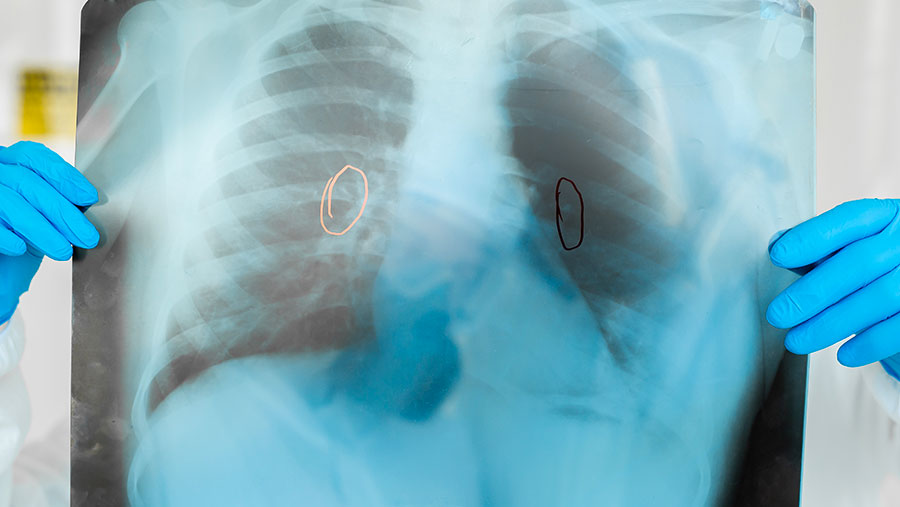

Bloomberg Technoz, Jakarta - Kanker paru-paru merupakan salah satu penyakit paling mematikan di dunia dan seringkali tidak menunjukkan gejala pada tahap awal.

Kanker paru-paru terjadi ketika sel-sel abnormal di dalam paru-paru tumbuh secara tidak terkendali dan membentuk tumor. Penyakit ini dapat menyerang siapa saja, meskipun lebih umum terjadi pada perokok aktif maupun pasif. Berdasarkan data dari WHO, kanker paru-paru adalah salah satu penyebab utama kematian akibat kanker secara global.